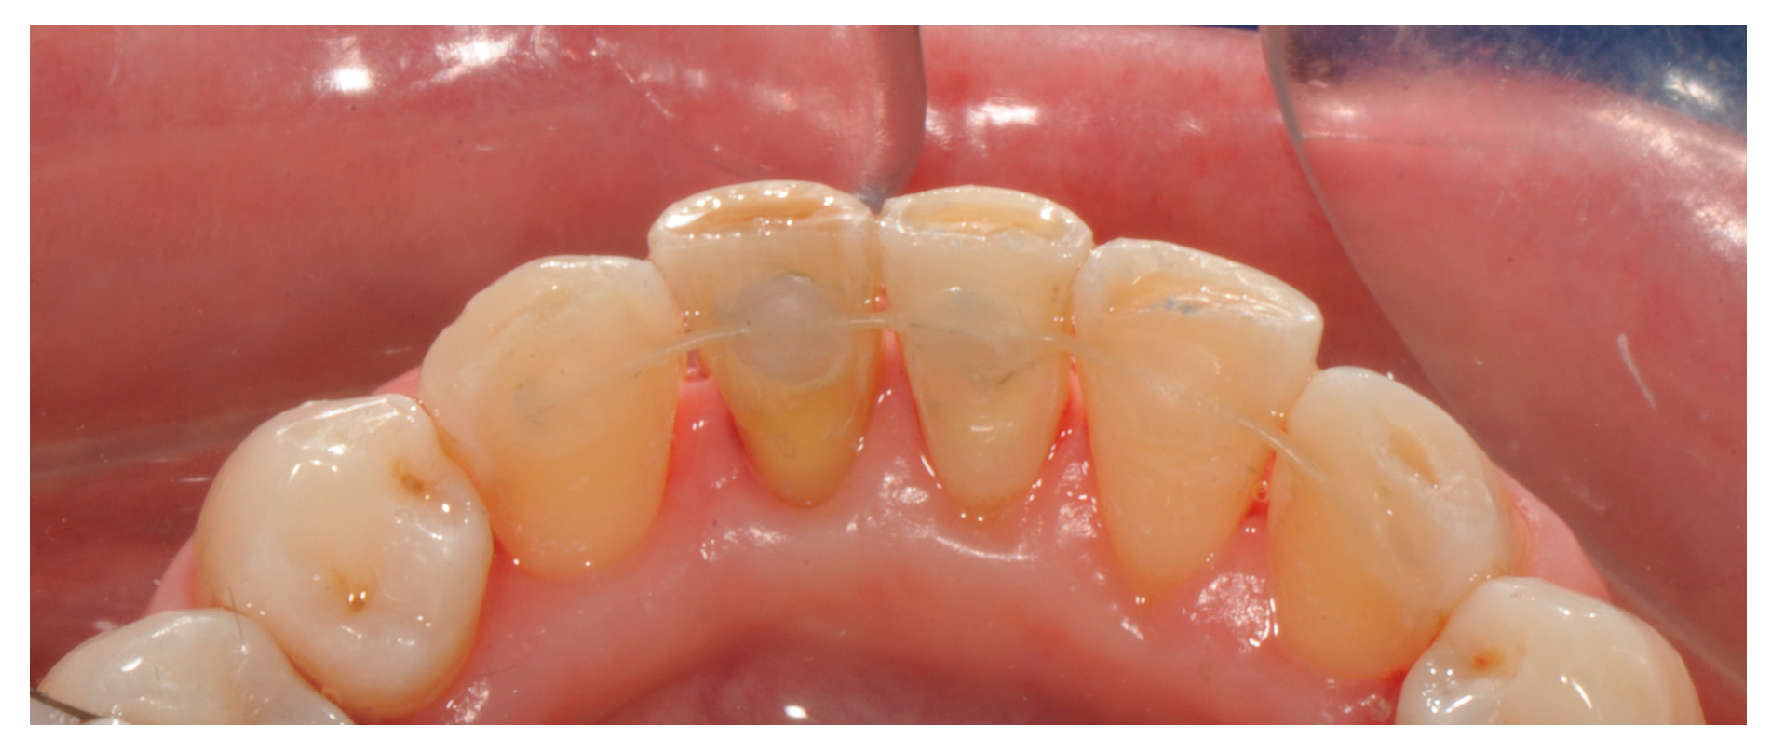

2. Materials and Methods